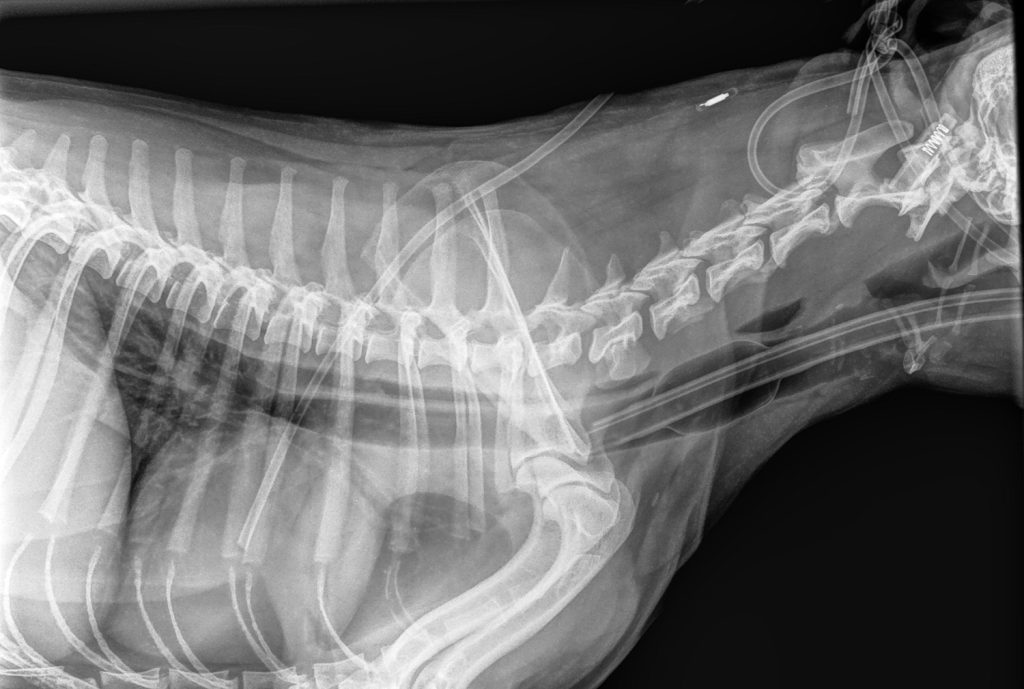

Klinisch konden we uitwendig niks afwijkends voelen of horen. De verdenking was dat hij iets in de slokdarm had zitten, dus in overleg met de eigenaar zijn er röntgenfoto’s gemaakt. Hierop was te zien dat er veel lucht in de maag zat en dat er mogelijk 1 tot 2 dingen in de slokdarm zaten. Dat betekende dat er gekeken moest worden of de structuren uit de slokdarm te krijgen waren.